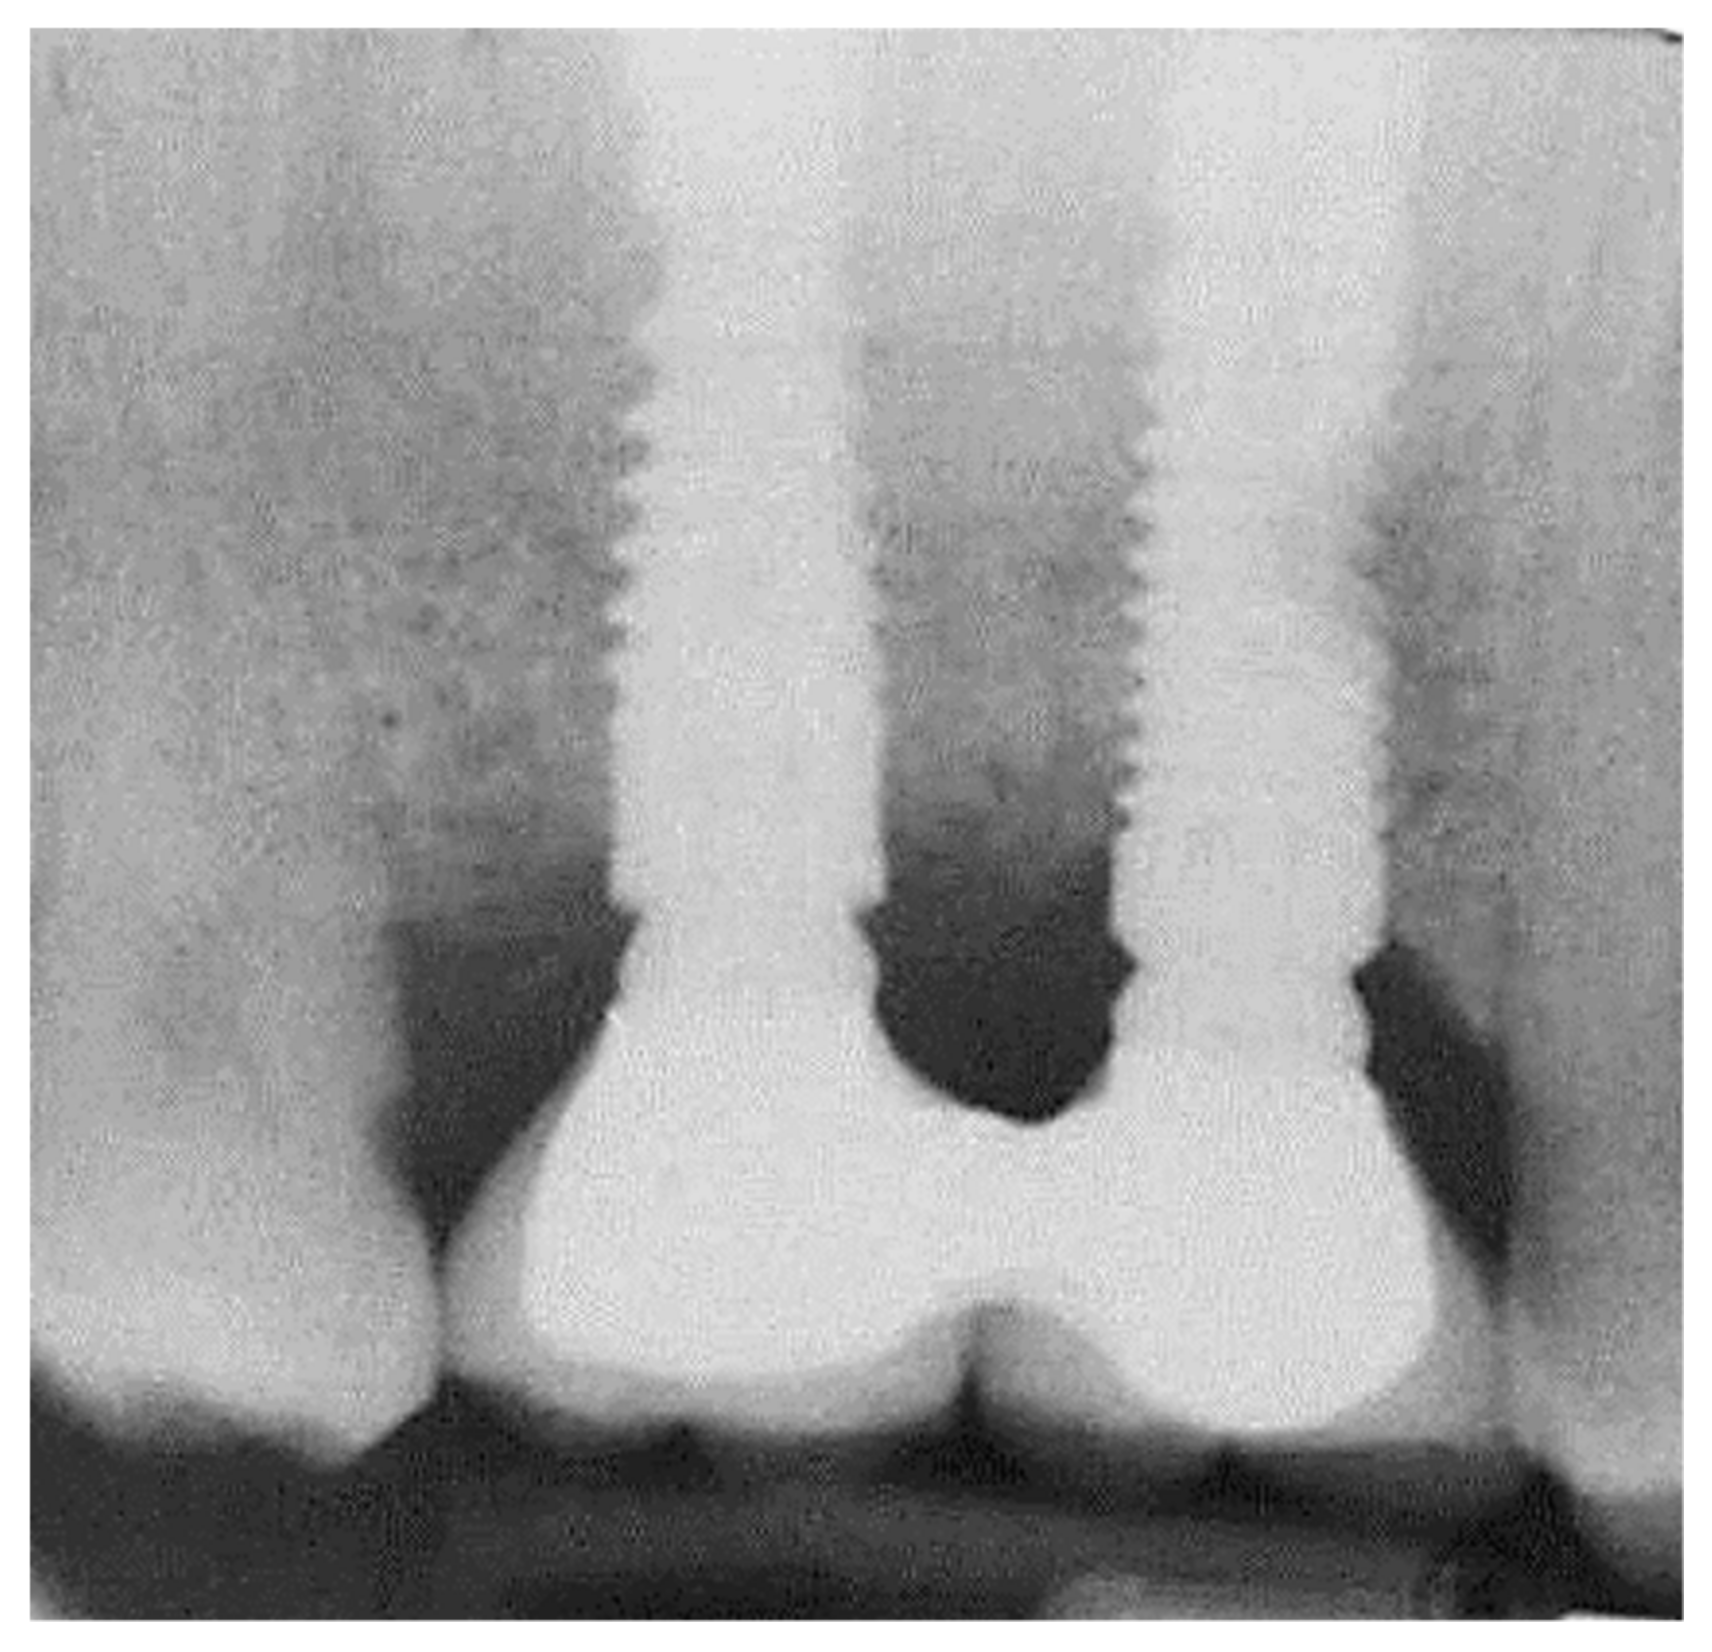

2.2. Marginal Bone Loss

2.3. Statistical Analysis